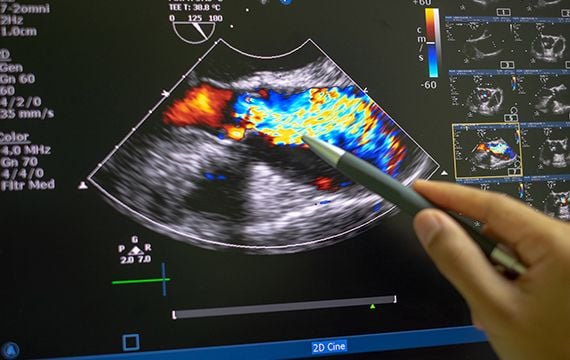

We connect a broad community of sonographers and clinicians who utilise cardiac ultrasound in the echo lab, the intensive care, the operating room, the emergency room and point-of-care.